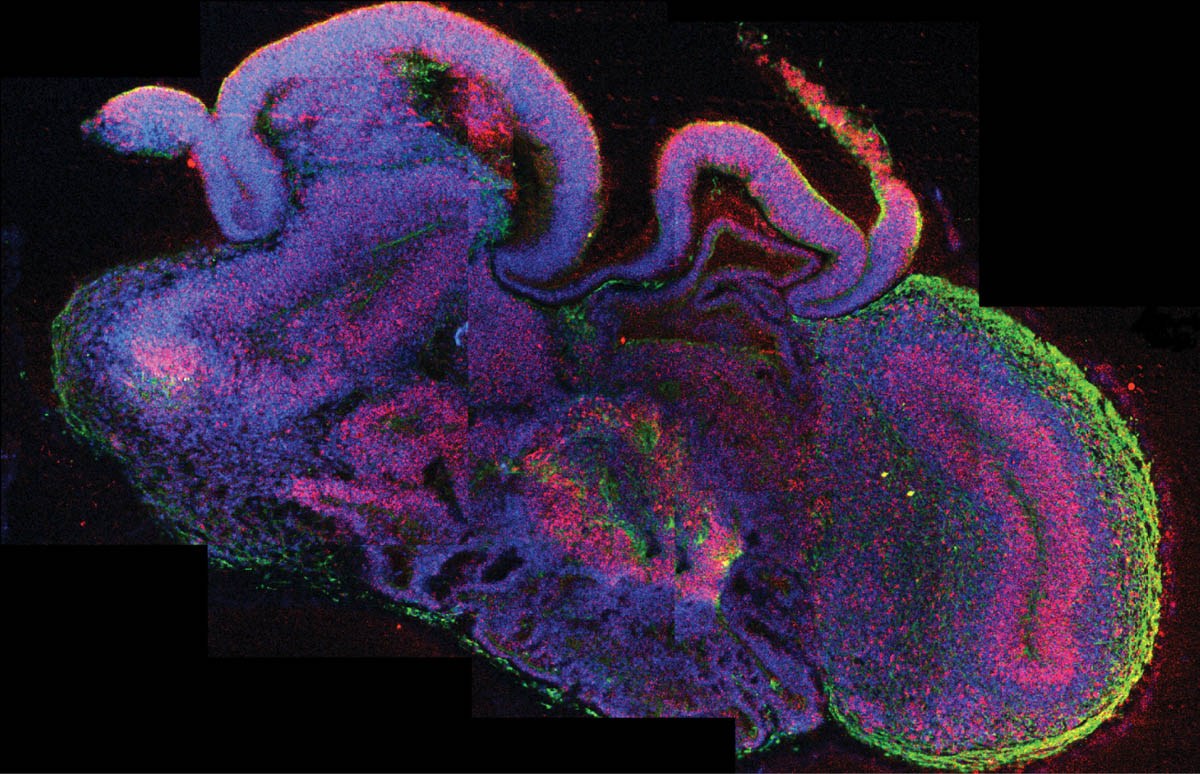

Hücre görüntüleme ve analitik sistemlerdeki ilerlemelerin artmasıyla ve aynı zamanda yeni iskele-matrikslerin kültür ortamlarında uygulanmasıyla birlikte, hücrelerin 3B modellerde büyümelerinde artış gözlemlenmektedir. Bu tür kültür ortamlarının in vivo doğal fizyolojik sistemlere daha yakın olduğu, bu nedenle birçok uygulama için yararlı materyal olduğu kanıtlanmıştır. Organoidler, bazı fizyolojik fonksiyonları koruyan mini, basitleştirilmiş organlar oluşturmak için belirli 3B ortamlarda yetişen hücreleri temsil etmektedir. Organa benzeyen anlamına gelen organoid terimi, Smith ve Cochrae tarafından kistik teratom vakasını tanımlamak için kullanıldığı 1946 yılının başlarında kullanılmıştır. Bundan sonraki yıllarda, kültür sistemlerinde organotipik yapılar organoid olarak kabul edilmiştir. Dolayısıyla, klasik gelişim biyolojisi çalışmalarında, sferoidler gibi 3B hücre agregatları, organoidler olarak tanımlanmasına rağmen bunlar in vivo doku yapısını tam olarak temsil etmemektedir. Yakın zamanda, ‘organoid’ terimi, kök hücrelerden gelişen, memelilerde orijinal dokunun in vivo mimarisini taklit eden kök hücrelerin çoklu soy farklılaşmasını sağlayan, kendiliğinden organize bir 3B yapı olarak kısmen kısıtlanmış bir anlam kazanmıştır.